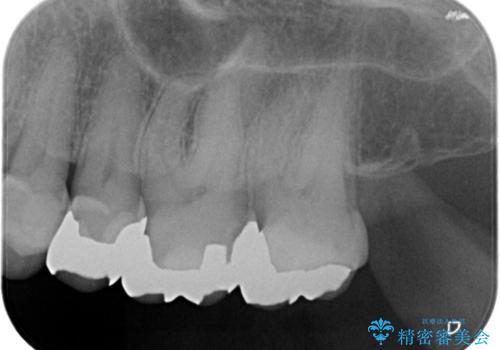

- 昔入れた銀歯のやりかえを主訴に来院されました。

セラミックインレーにて修復を行いました。

歯の強度を高めるためセラミッククラウンの提案もさせていただきましたが、患者様の希望でセラミックインレーにて修復を行なっております。